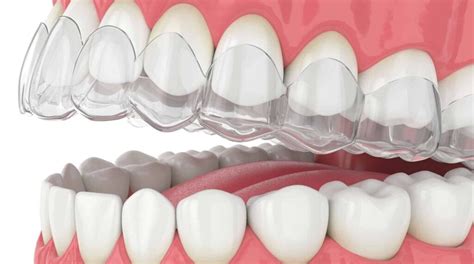

Retenedores Dentales Essix

Este tipo de soporte está hecho de plástico transparente moldeado y parece un alineador Invisalign. A la gente le gusta este tipo de retenedor dental porque es menos visible que una sujeción Hawley. Sin embargo, no es posible que los dientes superiores e inferiores se toquen de forma natural. Por esta razón, a algunos ortodoncistas no les gusta este tipo de retenedor.

Los retenedores Essix también tienen una vida útil más corta que los retenedores Hawley. En promedio, comienzan a desgastarse después de unos años y luego deben ser reemplazados.

Ventajas y Desventajas de los Retenedores Essix

- Ventaja: prácticamente invisible en los dientes.

- Desventaja: no permite que los dientes se toquen naturalmente. Se desgasta después de unos años. Puede ser difícil mantener limpias las superficies internas. Retiene el líquido en los dientes.